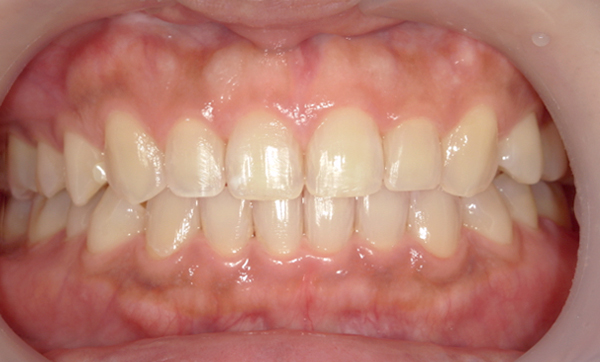

| 治療前 | 治療後 |

|---|---|

|